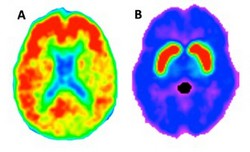

Imaging biomarkers for neurodegeneration

Recent research had revealed that the ageing brain undergoes prominent neurobiological changes such as white matter lesions, amyloid plaque build-up and decreased dopamine neurotransmitter function. Unfortunately, such changes are also seen in patients with neuropathologies such as dementia and Parkinson's, further complicating early diagnosis of disease. For instance, 20-50 % of clinically normal older people also have amyloid deposition in the brain, which is considered a hallmark pathology of Alzheimer’s disease. The EU-funded AMYDA (Disentangling the contributions of dopamine and amyloid burden to age-related changes in cognition and brain network connectivity in healthy older adults) project was initiated to find reliable imaging biomarkers of aging-related brain changes that can ultimately differentiate a “normal” brain from one that is in the preclinical stages of disease. AMYDA members assessed multiple imaging markers of the ageing brain using data form the Harvard Aging Brain study, collected at Harvard University and Massachusetts General Hospital. Surprisingly, results revealed that markers of white matter damage and markers of dopamine functions were not completely independent biomarkers of brain ageing. Mirroring the pattern for white matter damage, the dopamine system was found to be negatively impacted by high blood pressure. Also, studies confirmed that accumulation of cortical amyloid accelerates white matter damage, again suggesting that these markers are not separable and questioning the usefulness of studying these markers in isolation in the quest to diagnosing early Alzheimer's. Using techniques like functional magnetic resonance imaging (fMRI), researchers then explored the functional brain changes occurring in older individuals. The goal was to differentiate between healthy ageing and incipient neuropathology. Study outcomes revealed that biomarkers of fMRI functional connectivity were more sensitive and accurate than standard neuropsychological tests. In particular, fMRI of the midbrain–putamen functional connectivity in patients with Parkinson's disease revealed that this biomarker is proportional to the degree of neurodegeneration, providing hope that fMRI functional connectivity could be used as a biomarker of underlying neuropathology for early diagnosis. Results have already been published in over three journal articles. Given the steadily increasing elderly population, early detection and better treatment strategies are urgently needed as the socioeconomic burden of neurodegenerative disorders is extremely high. Further research exploiting human imaging to find neurodegenerative disease markers as well as therapeutic targets could help clinicians treat patients promptly and improve their quality of life.